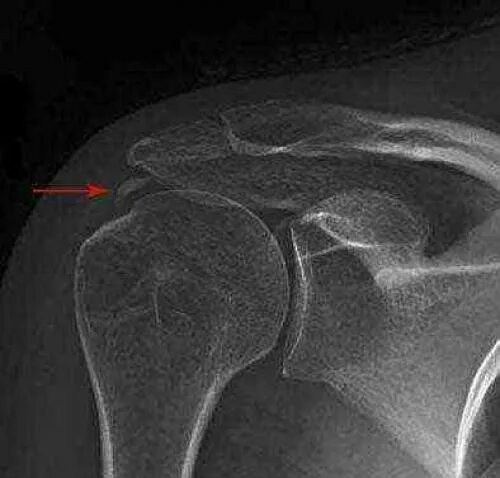

Обызвествление сухожилий мышц